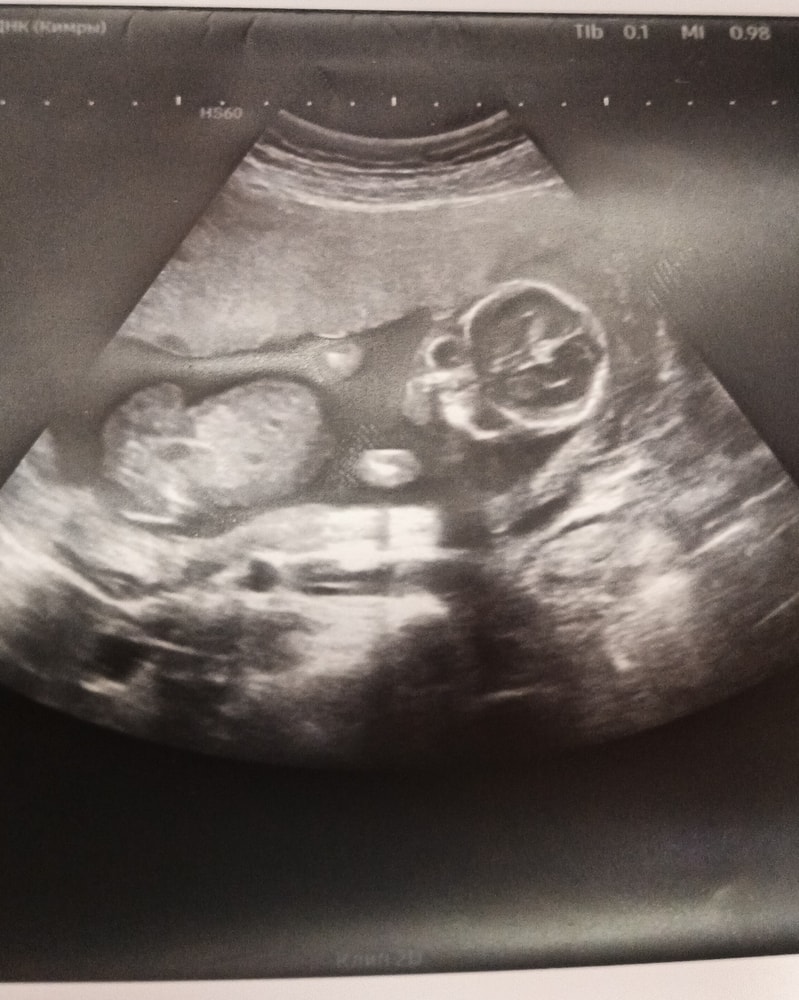

Как думаете девочка или мальчик?

Кто в животике живёт (гадаем по фото УЗИ; результаты НИПТ или УЗИ)Как думаете, девочка или мальчик?

Как думаете, девочка или мальчик?